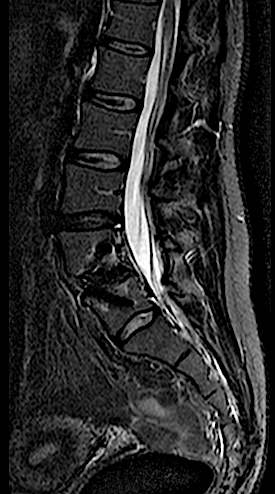

Paciente de 34 años con lumbalgia mecánica refractaria de años de evolución con progresión de la clínica.

En la RM lumbar de control se apreciaba edema en L5-L6 que se interpretó como secundario a sobrecarga mecánica a dicho nivel. Se decidió una fijación percutánea (MIS) L5-L6.